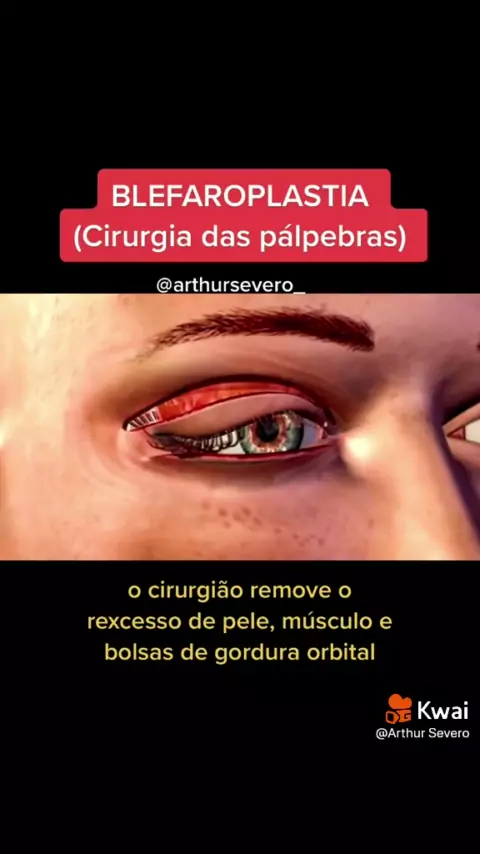

Fique por dentro... #necropsiaeeu #biomedicina #unicesumar #estudante #medicina

Fique por dentro... #necropsiaeeu #biomedicina #unicesumar #estudante #medicina